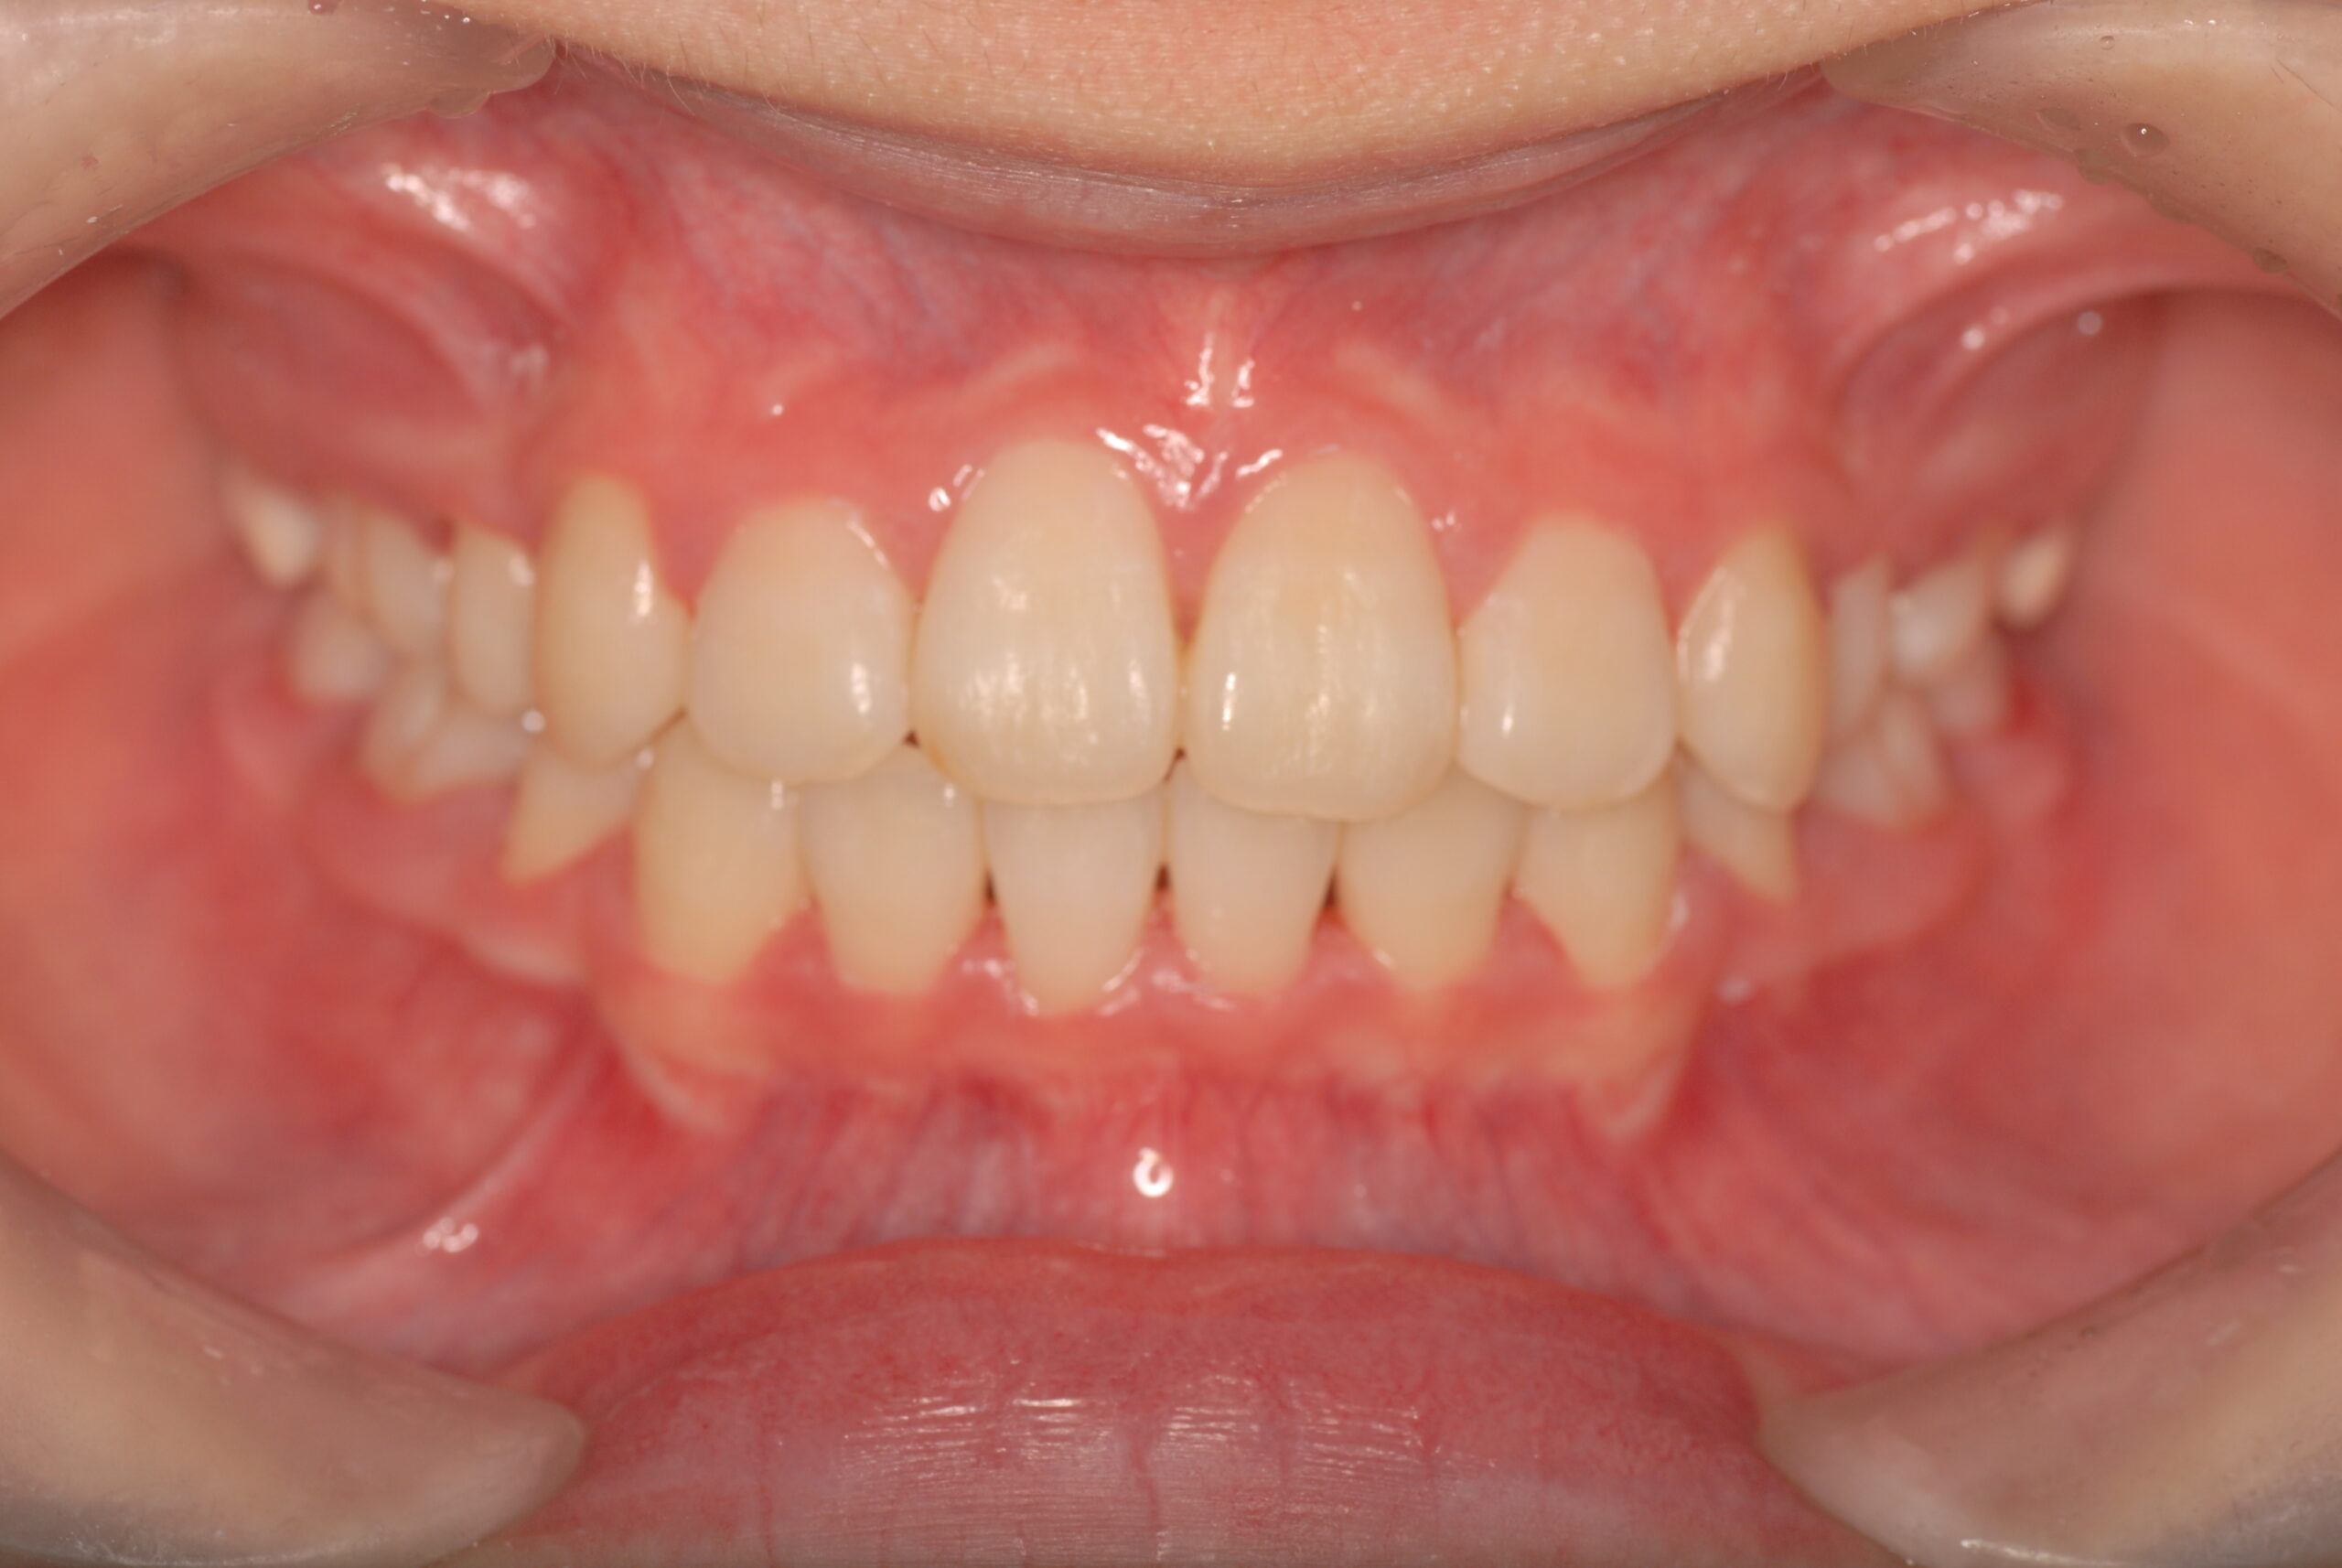

After

- 上顎前突、叢生。 上下顎第一小臼歯を抜歯し、抜歯空隙を利用し、顎外固定装置としてヘッドギヤを併用しながら、上顎前歯を可及的に後退させる。

- 治療期間、費用の目安

- 約3年6か月 約90万円+消費税(検査診断料、矯正料、ヘッドギヤ代、月1回の処置料の総額)

- リスク、副作用

- カリエス、歯肉炎、上顎前歯部後退の伴う歯根吸収、歯髄壊死、痛み